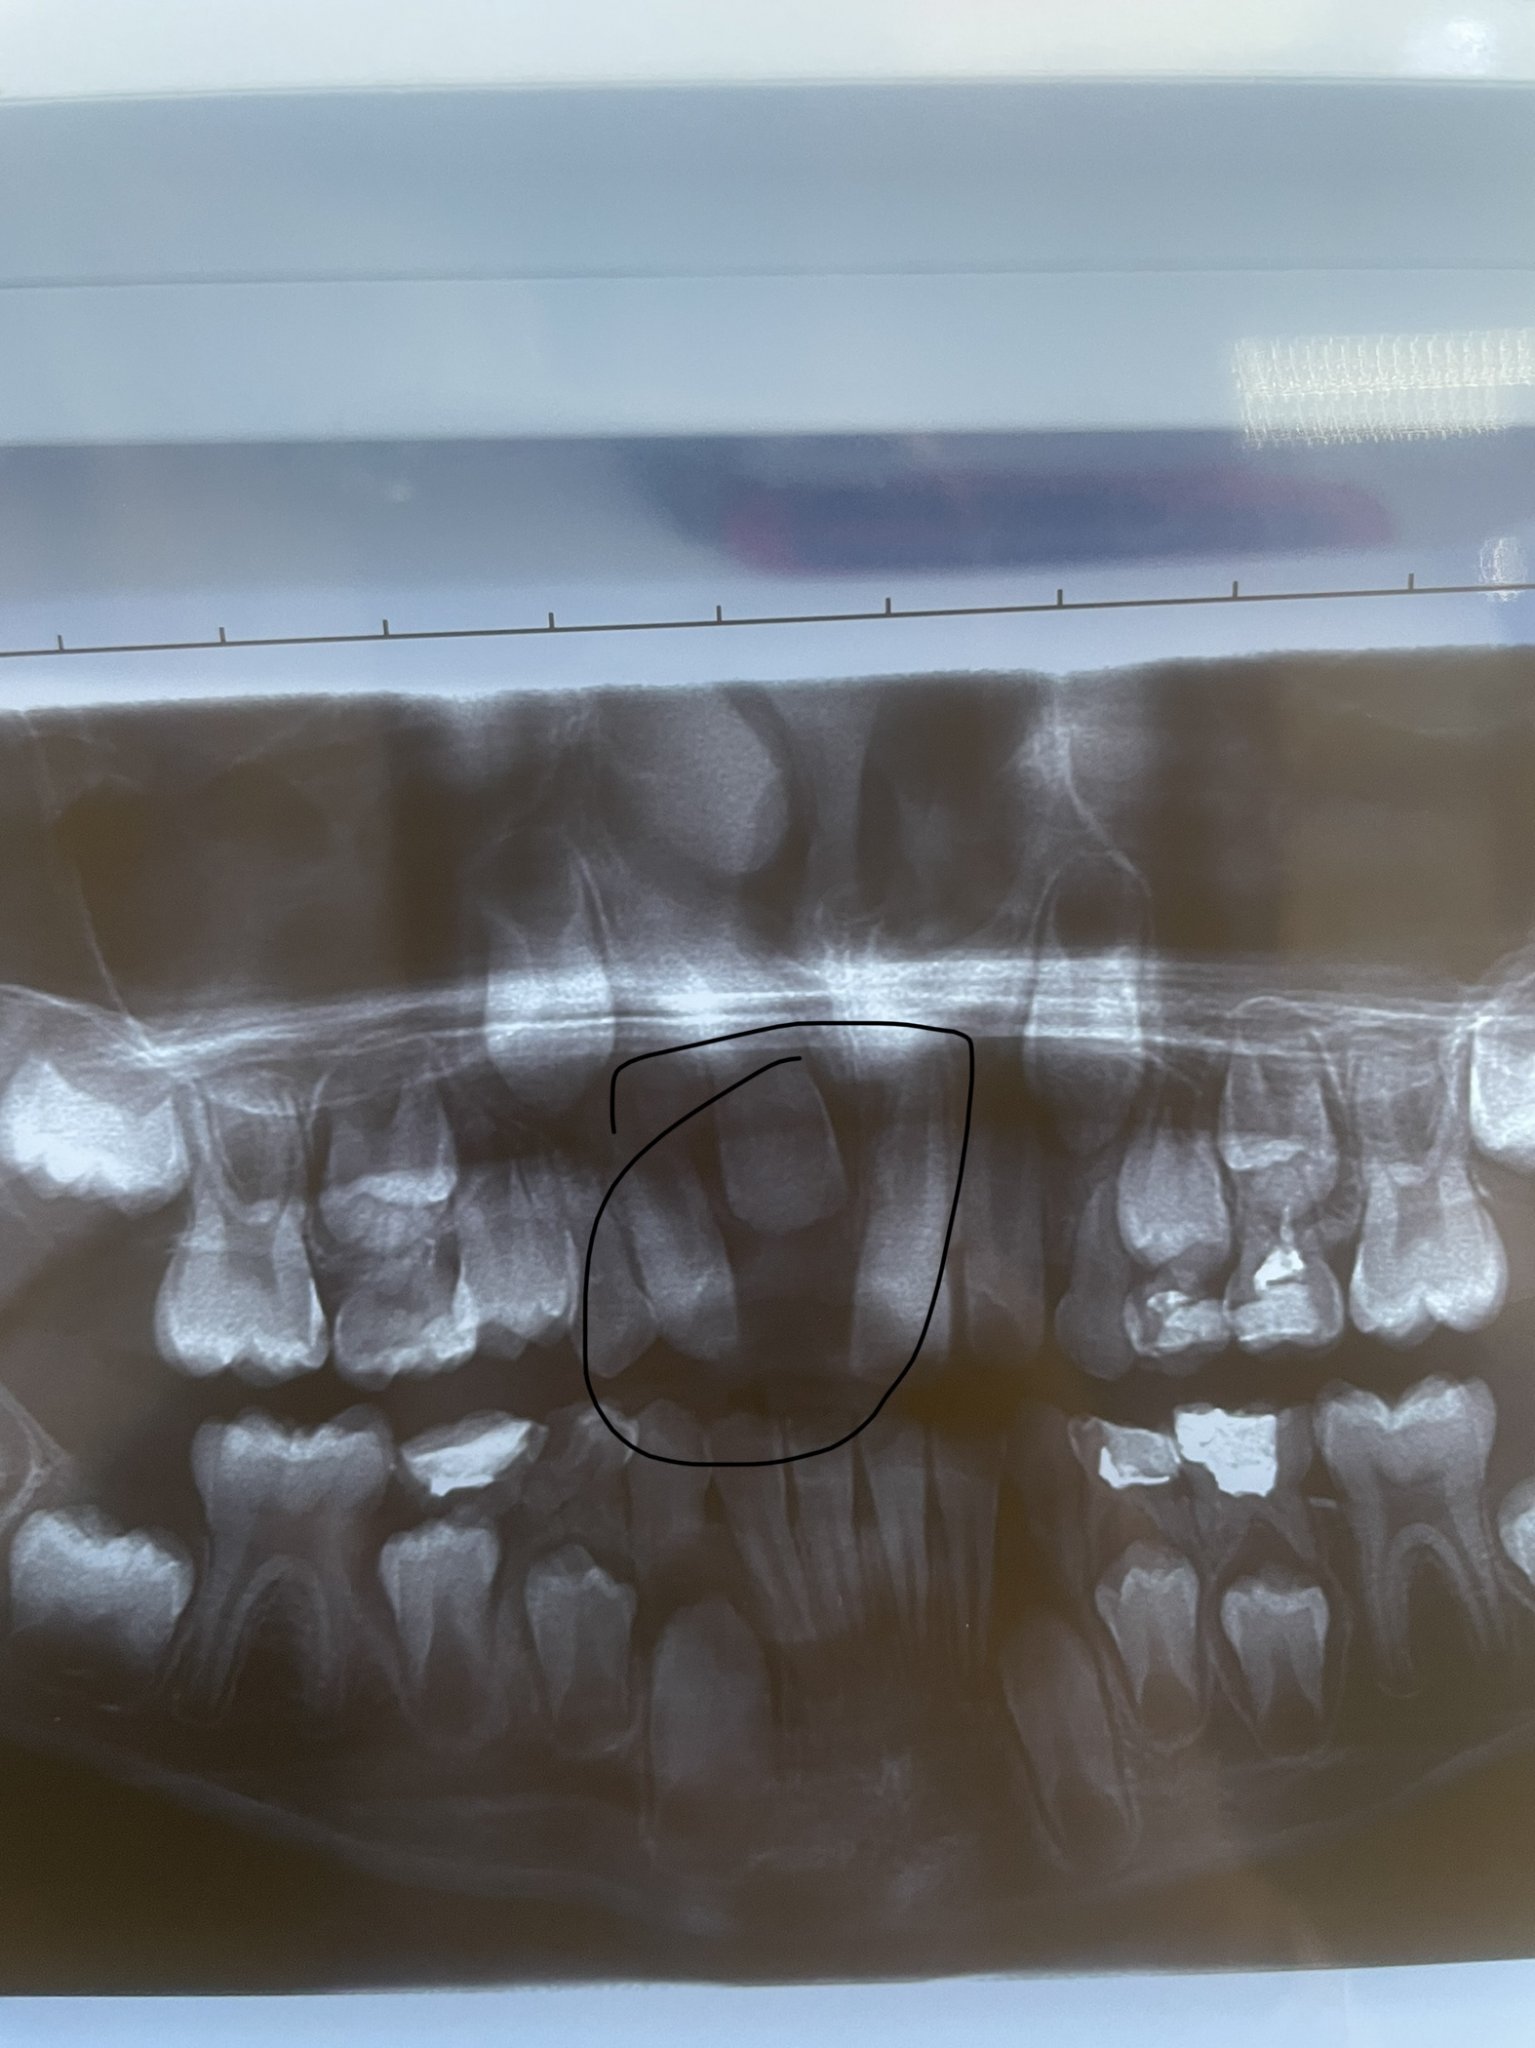

Кое е по-добро - импланти или мостове?

Имплантите и мостовете имат своите предимства и недостатъци. Имплантите често се рекламират, но не винаги са успешни в дългосрочен план. Те изискват определени условия на организма, които могат да увеличат шансовете за успешно интегриране в костта. Освен това поставянето на имплант може да бъде по-скъпо и не гарантира по-голям процент на успеваемост. Мостовете, от друга страна, могат да бъдат поставени по-бързо и по-евтино, но изискват изпиляване на съседните зъби. Всеки случай трябва да бъде оценен индивидуално от имплантолог, който може да предложи най-подходящото решение за конкретния случай.